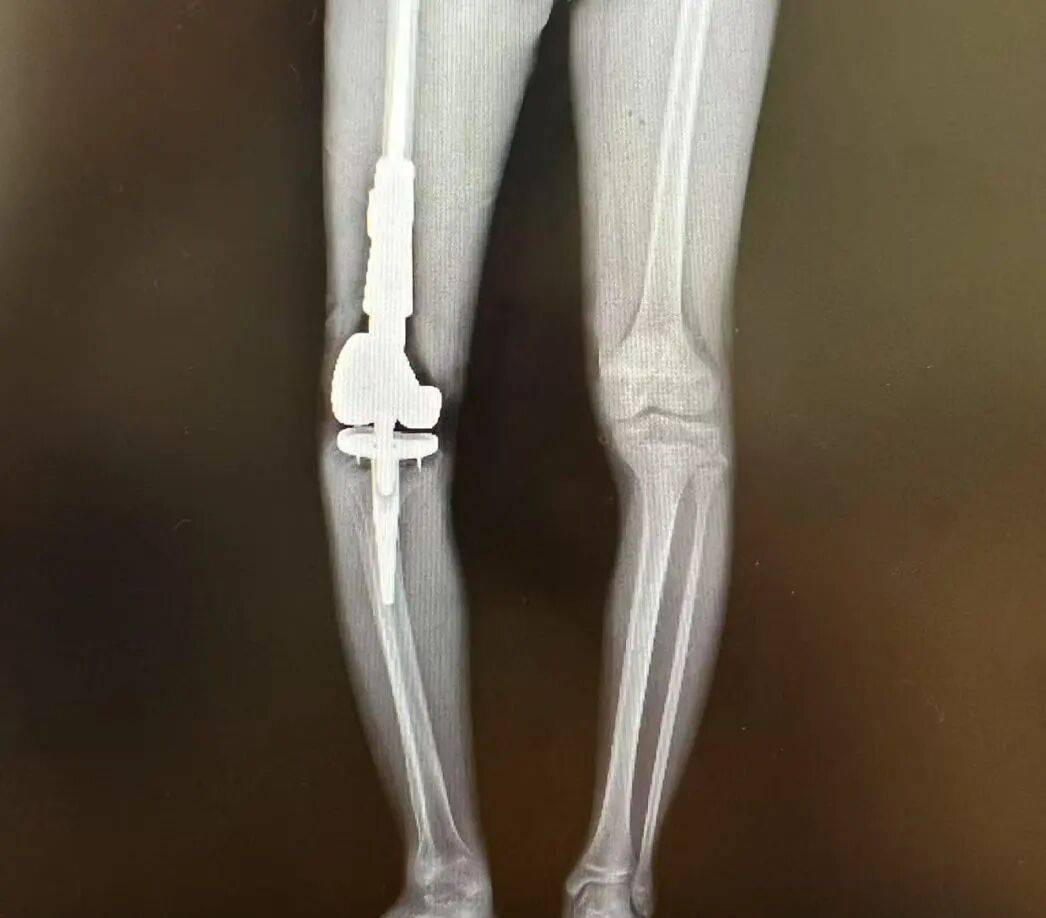

浙大儿院骨科副主任陈建松副主任医师介绍,骨癌的治疗充满挑战。几十年前,治疗骨癌确实需要截肢。如果癌细胞还没扩散,通过截肢,虽然命保牢了,但是腿没了。现在,我们采取综合治疗方案,目标是既要保命,又要保腿。”陈建松主任解释道,“第一步通过手术活检确认骨癌病理结果。第二步,通过两个疗程的化疗,降低骨癌细胞的生物活性,以及杀灭可能存在的微小转移灶。第三步,行骨癌根治手术,彻底切除肿瘤,然后用量身定制的人工关节替代被切除的骨头,保住腿;第四步是术后继续化疗,清除可能残留的癌细胞,预防肿瘤复发,保住命。”

手术中切除的骨癌部位和替代的人工关节

在浙大儿院莫干山院区,由陈建松副主任主刀,小宇成功进行了右股骨远端骨肿瘤根治术+人工膝关节置换术,术后小宇情况稳定,切口愈合良好。现已转入肿瘤内科进行下阶段的化疗。